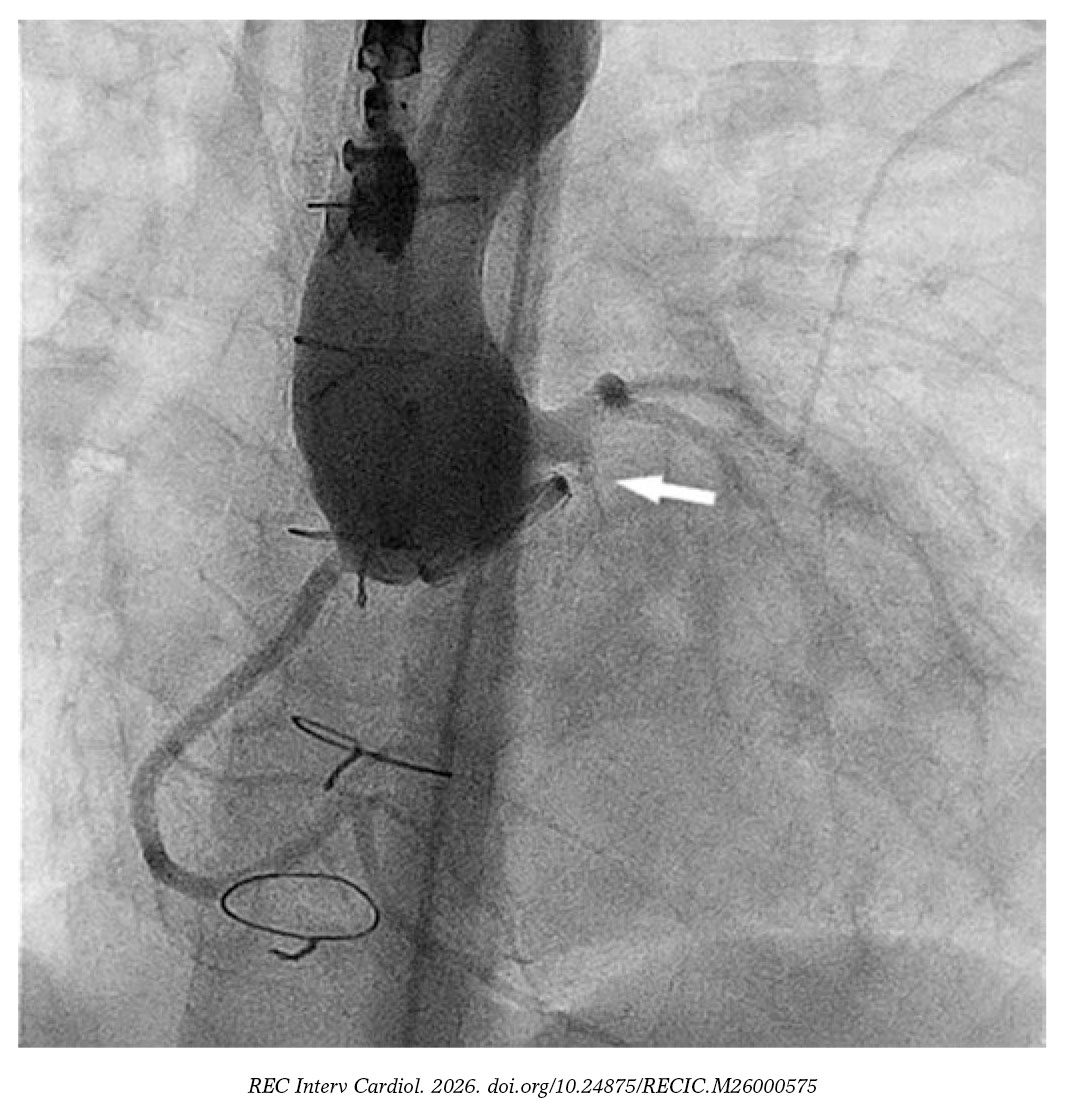

En la aortografía inicial no se detectó la fuga periprotésica, pero sí una dilatación del tronco coronario izquierdo de 6,5 mm y una fístula de este al ventrículo izquierdo de 2,4 mm de diámetro y 4,5 mm de longitud (figura 1 y vídeo S1).

Figura 1.